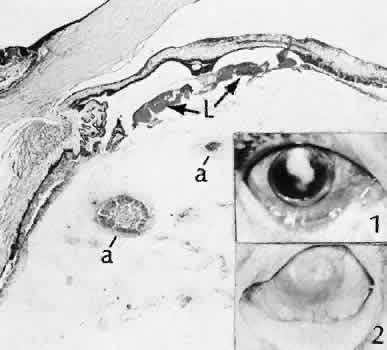

Fig. 49. Two cases of fungal endophthalmitis following cataract extraction. This is a case of extracapsular cataract extraction in which phacoemulsification was not used. The eye became inflamed 2 months after the procedure and was enucleated 2 weeks later. Multiple fungal abscesses (a) are present in the anterior vitreous. Inset 1 is characteristic of the presentation of fungal endophthalmitis with a well-defined anterior chamber infiltrate associated with minimal signs of inflammation. Inset 2 is illustrative of advanced tissue destruction associated with the inflammatory reaction to fungal organisms.